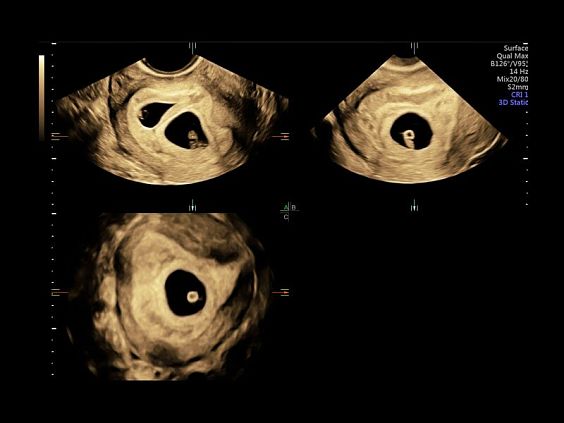

Клинические изображения

• Программа 3D и режим инверсии (при наличии специализированных датчиков)

• Программа объемной визуализации плода классический HD-Live + расширенный пакет Hdlive Silhouette и Studio:

• HDlive Flow - перемещаемый источник света, совместимый с визуализацией кровотока в 3D

• HDlive Silhouette - режим "Силуэт" с подчеркиванием границ тканей и объектов, "объем в объеме"

• HDlive Flow Silhouette - режим "Силуэт" с выделением границ полостей сердца и сосудов, совместимый с визуализацией кровотока

• HDlive Studio - три независимых источника освещения с регулировкой интенсивности